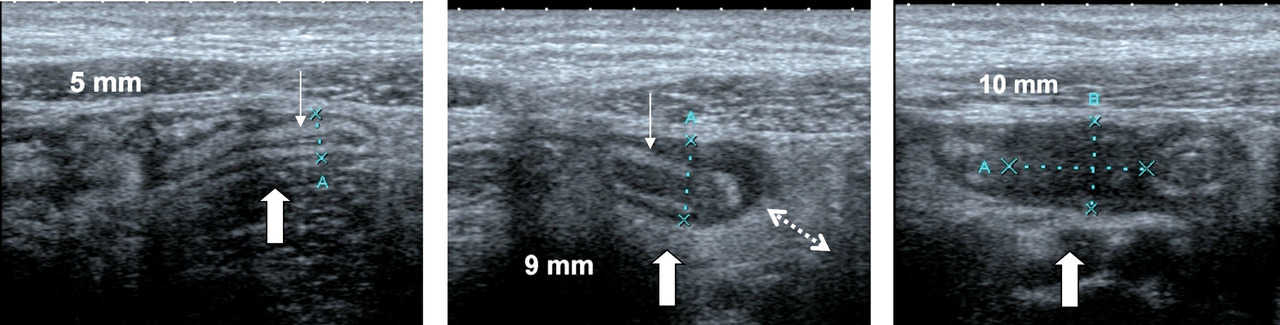

à Échographie avec compression dosée :

– non irradiante, peut être répétée ;

– l’examen de l’ensemble de l’abdomen peut montrer d’autres lésions : fréquentes (hyperplasie lymphoïde, lymphadénite) ou rares (tumeur, kyste du cholédoque), évitant chirurgie et appendicectomie inutiles ;

– critères consensuels : importance d’un examen exhaustif de la valvule à la pointe (figure ) ;

– permettrait de limiter à 8 %, sans erreur par défaut, le taux de chirurgies superflues ;

– autre avantage : précise la topographie de l’appendice malade et d’éventuelles collections.